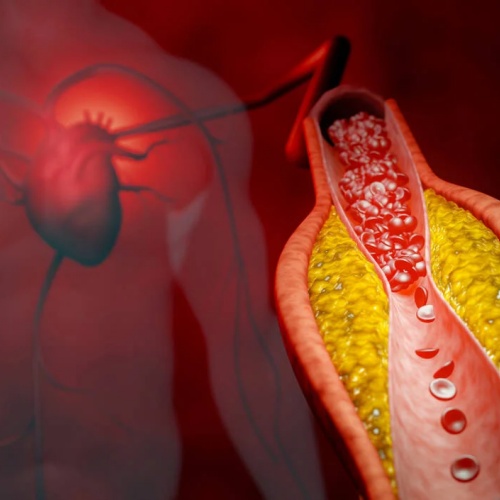

在众多血脂指标中,脂蛋白(a)(Lipoprotein(a),简称Lp(a))近年来越来越受到关注。它的结构与低密度脂蛋白(LDL,即“坏胆固醇”)非常相似,但多了一个关键成分——载脂蛋白(a),并与载脂蛋白B-100以共价方式结合。

正是这一结构,使Lp(a)具有更强的致动脉粥样硬化作用。大量研究表明: